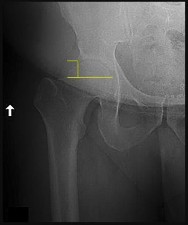

A 12-year-old male with a BMI > 95th percentile presents with hip pain and is diagnosed with a Slipped Capital Femoral Epiphysis (SCFE). Which of the following is the strongest indication for prophylactic in situ pinning of the asymptomatic contralateral hip?

Explanation

Prophylactic pinning of the contralateral hip in SCFE is controversial but is strongly indicated in patients with underlying endocrinopathies (e.g., hypothyroidism, growth hormone deficiency) or renal osteodystrophy. These conditions dramatically increase the risk of bilateral involvement. Other indications include inability to follow up, radiation therapy, and open triradiate cartilage (though age and triradiate status are debated, endocrinopathy is universally agreed upon).